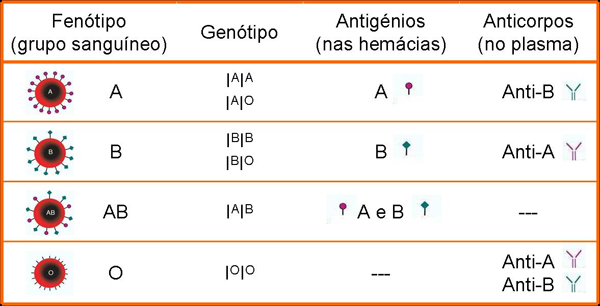

Cada indivíduo apresenta na membrana das suas hemácias e no plasma proteínas diferentes determinadas geneticamente, as quais se denominam antigénios e anticorpos, respetivamente. As diferenças no tipo de sangue de diversos indivíduos foram comprovadas por Karl Landsteiner (cientista austríaco) no início do século XX, permitindo a classificação dos grupos sanguíneos ou tipos sanguíneos. Na população existem três formas alélicas possíveis (IA, IB e IO) que originam quatro fenótipos sanguíneos (A, B, AB e O), constituindo assim o denominado Sistema ABO (figura 2). O sistema ABO é, portanto, um caso de alelos múltiplos. No entanto, cada indivíduo apenas possui dois alelos, herdados dos seus progenitores. Para além do polialelismo, o sistema sanguíneo ABO inclui ainda um exemplo de co-dominância em que os alelos A e B se expressam simultaneamente. O alelo O é recessivo em relação aos alelos A e B.

Figura 2 – Características dos grupos sanguíneos (Sistema ABO).

A expressão fenotípica das formas alélicas, que determinam o grupo sanguíneo de um indivíduo, resulta na presença de antigénios A e/ou B na membrana das hemácias e anticorpos no plasma (anti-A ou anti-B). O tipo sanguíneo O não apresenta antigénios na membrana das hemácias mas apresenta ambos os anticorpos no plasma. O tipo sanguíneo AB apresenta ambos os antigénios na membrana das hemácias, mas não contém anticorpos no plasma. Estas características vão determinar a compatibilidade ou incompatibilidade sanguínea, uma vez que se estiverem presentes o mesmo tipo de antigénio e anticorpo, as hemácias vão aglutinar com os anticorpos. O processo de aglutinação consiste na reação entre um anticorpo presente ou produzido no plasma (aglutinina) e os antigénios presentes na membrana das hemácias (aglutinogénio), formando um aglomerado de pequenas massas de células. Por esta razão, o portador do tipo sanguíneo O é um dador universal e o portador do tipo sanguíneo AB é um recetor universal (figura 3).